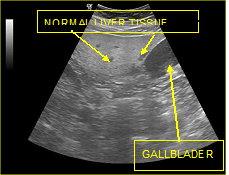

The fatty infiltration of the liver is shown on ultrasound with significantly increased echogenicity "bright liver", in comparison with the right kidney cortex (Figure 1). Normally, the liver and the renal cortex have similar echogenicity, relative to the parenchyma of the pancreas and the spleen. The maximum diameter of the liver in the midclavicular line (MCL) was increased, right lobe>15 cm (Figure 5). Also significant features are the absence of mass effect on intrahepatic vasculature (Figure 6) as well as the poor visualization of the deep parts of the liver (Figure 7), due to decreased permeability of the acoustic beam. A focal or diffuse morphology has been shown to increase the echogenicity of the fatty liver. Differential diagnosis is caused by focal fat infiltration (Figure 8), which has a geographic distribution. In this case, hypoechoic areas correspond to normal hepatic parenchyma on fatty infiltration sites, whereas, normal parenchyma islets can easily be identified due to their typical positions, in front of the right branch of the portal vein, its division, around the area of the gallbladder and the caudate lobe.9−13

Figure 8 Focal fat infiltrations Islands of normal liver tissue within a sea of hepatic steatosis (presence of regions with normal echogenicity (islands) in the lipid-infiltrated parenchyma (sea).